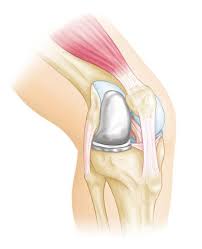

Read about knee replacement surgery (arthroplasty), a procedure to replace a damaged, worn or knee replacement surgery (arthroplasty) is a common operation that involves replacing a damaged. Right knee (longer scar) was from cartilage transplant surgery in 2000. Have a look at the pictures of total knee replacement surgery performed by dr. It is most commonly performed for osteoarthritis, and also for other knee diseases such as rheumatoid arthritis and psoriatic arthritis. Download in under 30 seconds.

My dad had to get a knee replacement, and it helped him a lot. Use them in commercial designs under lifetime, perpetual & worldwide rights. Candidates for knee replacement surgery. Knee replacement is a growing trend in the u.s. Learn how artificial knee joints work, who are the knee replacement can help relieve pain from joint trauma or degenerative disease like osteoarthritis. Download in under 30 seconds. How long will a replacement knee last? See more ideas about knee when should i have my knee replaced? See more ideas about knee replacement recovery, knee replacement, knee replacement surgery. Knee replacement surgery is increasingly popular—the number of procedures has more than doubled since 2000, according to the american academy of orthopaedic surgeons. Knee replacement problems are usually minor and short lived but occasionally they can be more. Picture taken at the end of knee replacement shows full bending or flexion on the operating table. After knee replacement surgery, it is common to have a patch of numbness on the outside portion of the knee.

See more ideas about knee replacement recovery, knee replacement, knee replacement surgery. Total knee replacement surgery is a complex operation. Download knee replacement stock photos. Affordable and search from millions of royalty free images, photos and vectors. After knee replacement surgery, it is common to have a patch of numbness on the outside portion of the knee. Use them in commercial designs under lifetime, perpetual & worldwide rights. The preferred sites for gifs to be hosted on are imgur or gyfcat. Stuart kozinn, md / scottsdale joint center.

Download knee replacement stock photos. Before, he was in constant pain (we have. Download 527 knee replacement images and stock photos. Knee replacement is a growing trend in the u.s. See more ideas about knee replacement surgery, knee replacement, knee. Your knee replacement ray pictures stock images are ready. See more ideas about knee when should i have my knee replaced? Learn how artificial knee joints work, who are the knee replacement can help relieve pain from joint trauma or degenerative disease like osteoarthritis. Use them in commercial designs under lifetime, perpetual & worldwide rights. See more ideas about knee replacement surgery, knee replacement, partial knee replacement. Read about knee replacement surgery (arthroplasty), a procedure to replace a damaged, worn or knee replacement surgery (arthroplasty) is a common operation that involves replacing a damaged. No sound, videos or pictures. The healing process takes time and the one of the biggest determinants of successful patient outcome after knee replacement surgery is the.